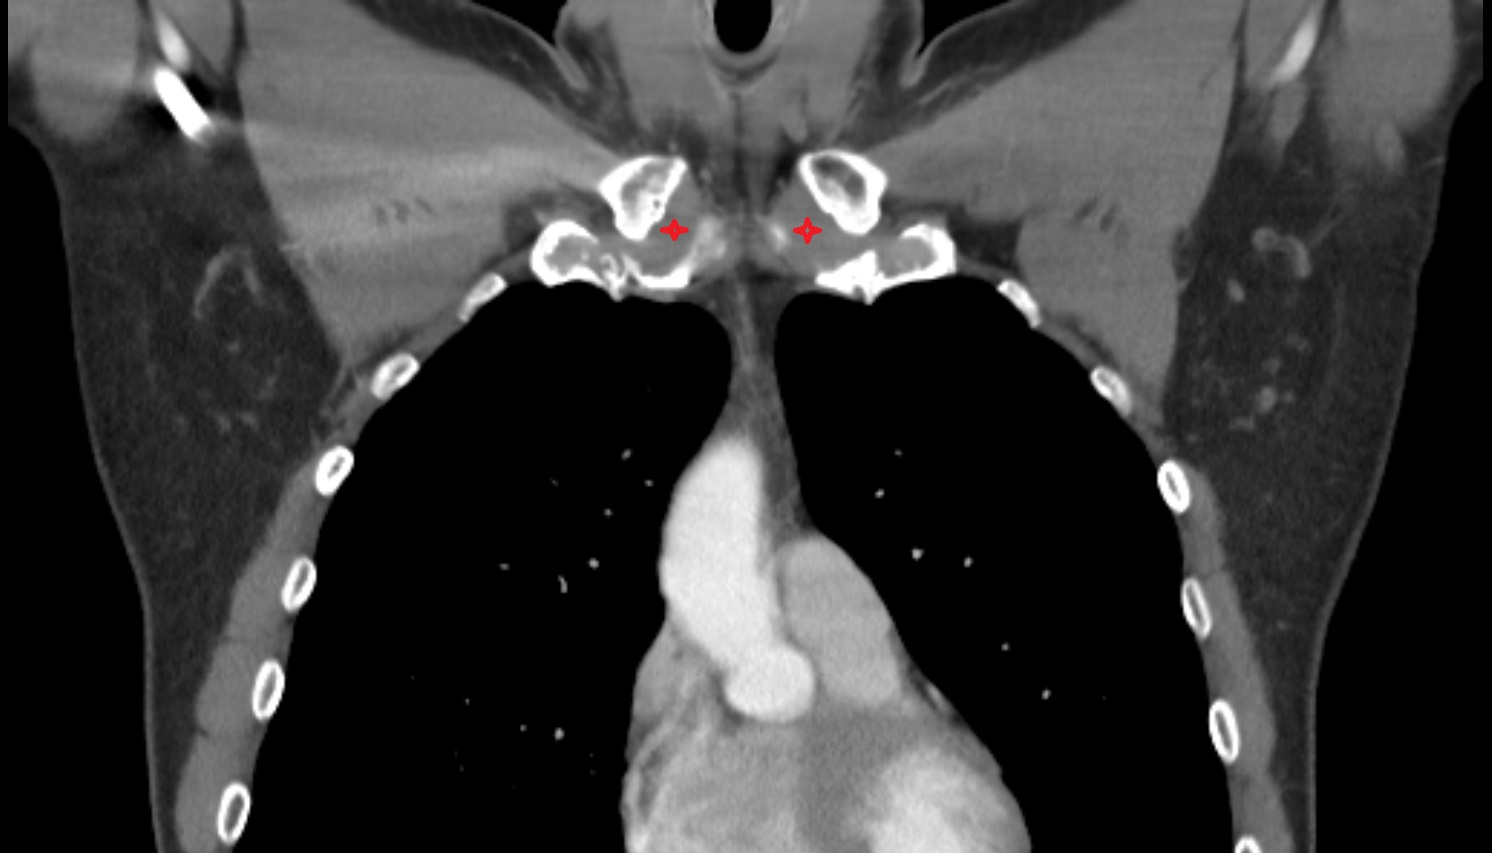

- Carotid bifurcation

- Common carotid artery

- External carotid artery

- Internal carotid artery (cervical part)